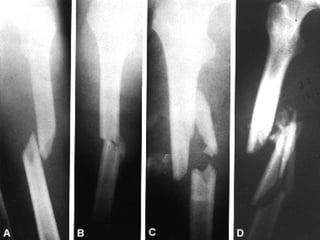

EXTENSION Completa Incompleta (fisuras, abombamiento y tallo verde

TIPO DE TRAZO

RELACION DE LOS FRAGMENTOS ENTRE SI Sin desplazamiento Con desplazamiento: lateral, angulada, rotación, diastasado, cabalgado, impactada